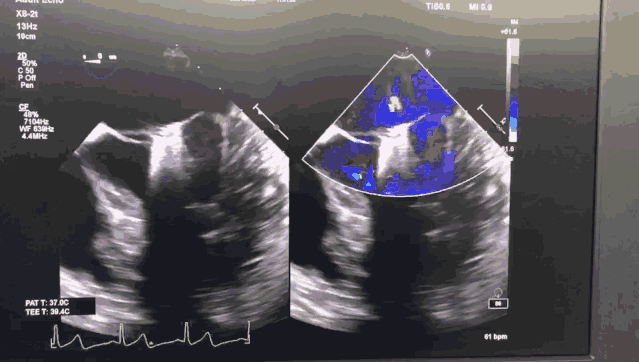

图1 ValveClamp术前经食道心超

图2 ValveClamp术后经食道心超